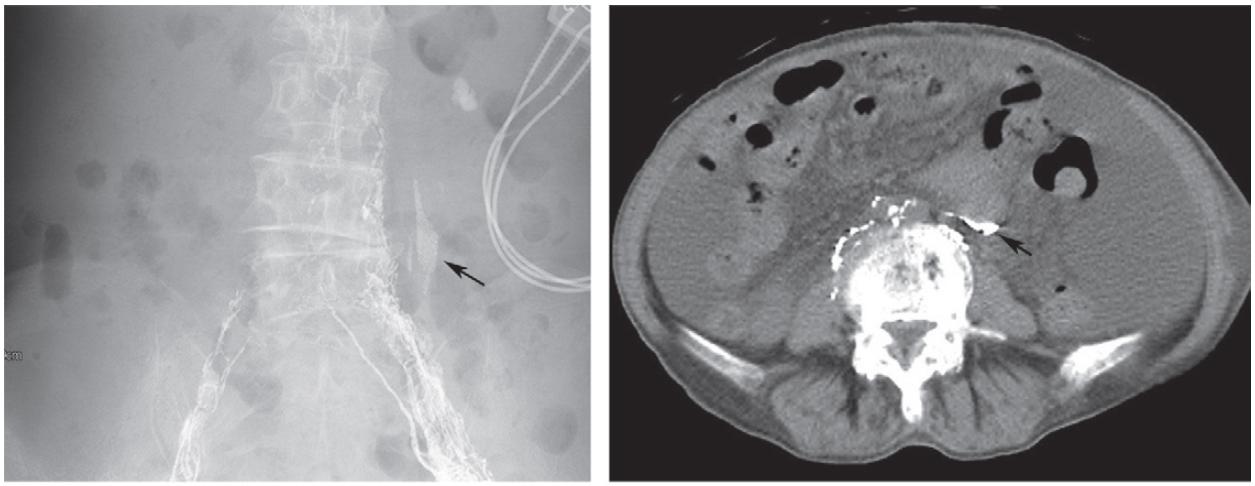

复发/难治性盆腔淋巴囊肿可尝试应用淋巴管栓塞术。在超声引导下,应用微穿针穿刺,微穿针远端置于淋巴结皮质与髓质之间,经微穿针缓慢注入超液化碘油,DSA密切监测淋巴管显影情况,必要时术中CBCT监测淋巴管显影。

当实时显影出现与淋巴囊肿相连接的淋巴管时即可进行栓塞治疗。淋巴管栓塞治疗术后仍需密切观察淋巴囊肿引流量。

淋巴管造影+栓塞治疗